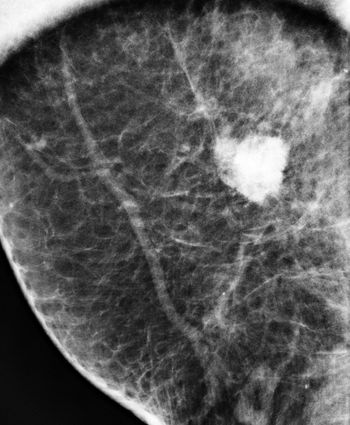

A 46-year-old patient presented for a second opinion on a mass found within the right breast on a prior outside mammogram. The patient denies any lumps or pain within either breast.